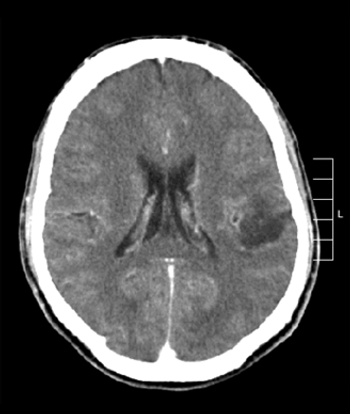

Adding rindopepimut to bevacizumab therapy was associated with improved long-term survival in patients with recurrent EGFRvIII-positive glioblastoma.